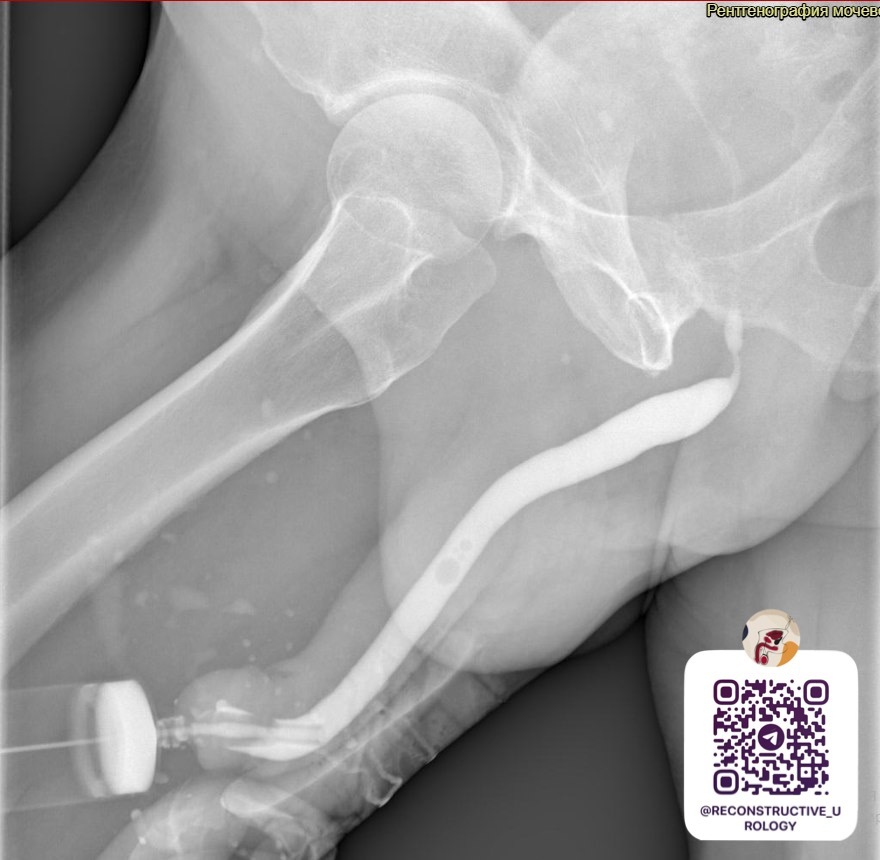

Ретроградная уретрография - критическое сужение в области проксимального бульбозного отдела уретры, протяженностью 12 мм.

Диагноз: Стриктура проксимального бульбозного отдела уретры.